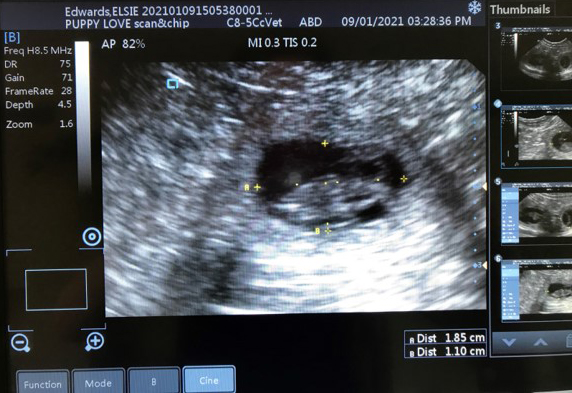

Pregnancy Scanning

Ultrasound scans are a non-invasive, safe and painless procedure, used at various stages of pregnancy to gain greater insight and highlight potential problems that may occur.

To perform the scans I use a VIS Scan Pad + veterinary grade scanner (endorsed by the Animal Ultrasound Association) that offers superior image quality optimised for pregnancy detection & complies with international standards on ultrasonic safety.

• Estimate the size of litter, foetal viability and due date.

• High resolution images and videos emailed as a keepsake included in the price.